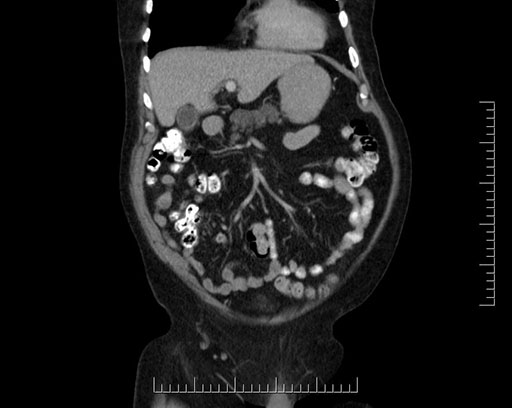

Imaging Analysis

Look through the patient's CT scan to identify any areas of concern for the necessary procedure.

Based on your CT findings, which issue(s) would give reason for "planned slowing down moment(s)" in this case?

Considering a standard Whipple procedure, what step(s) of the operation would you do differently in this case?